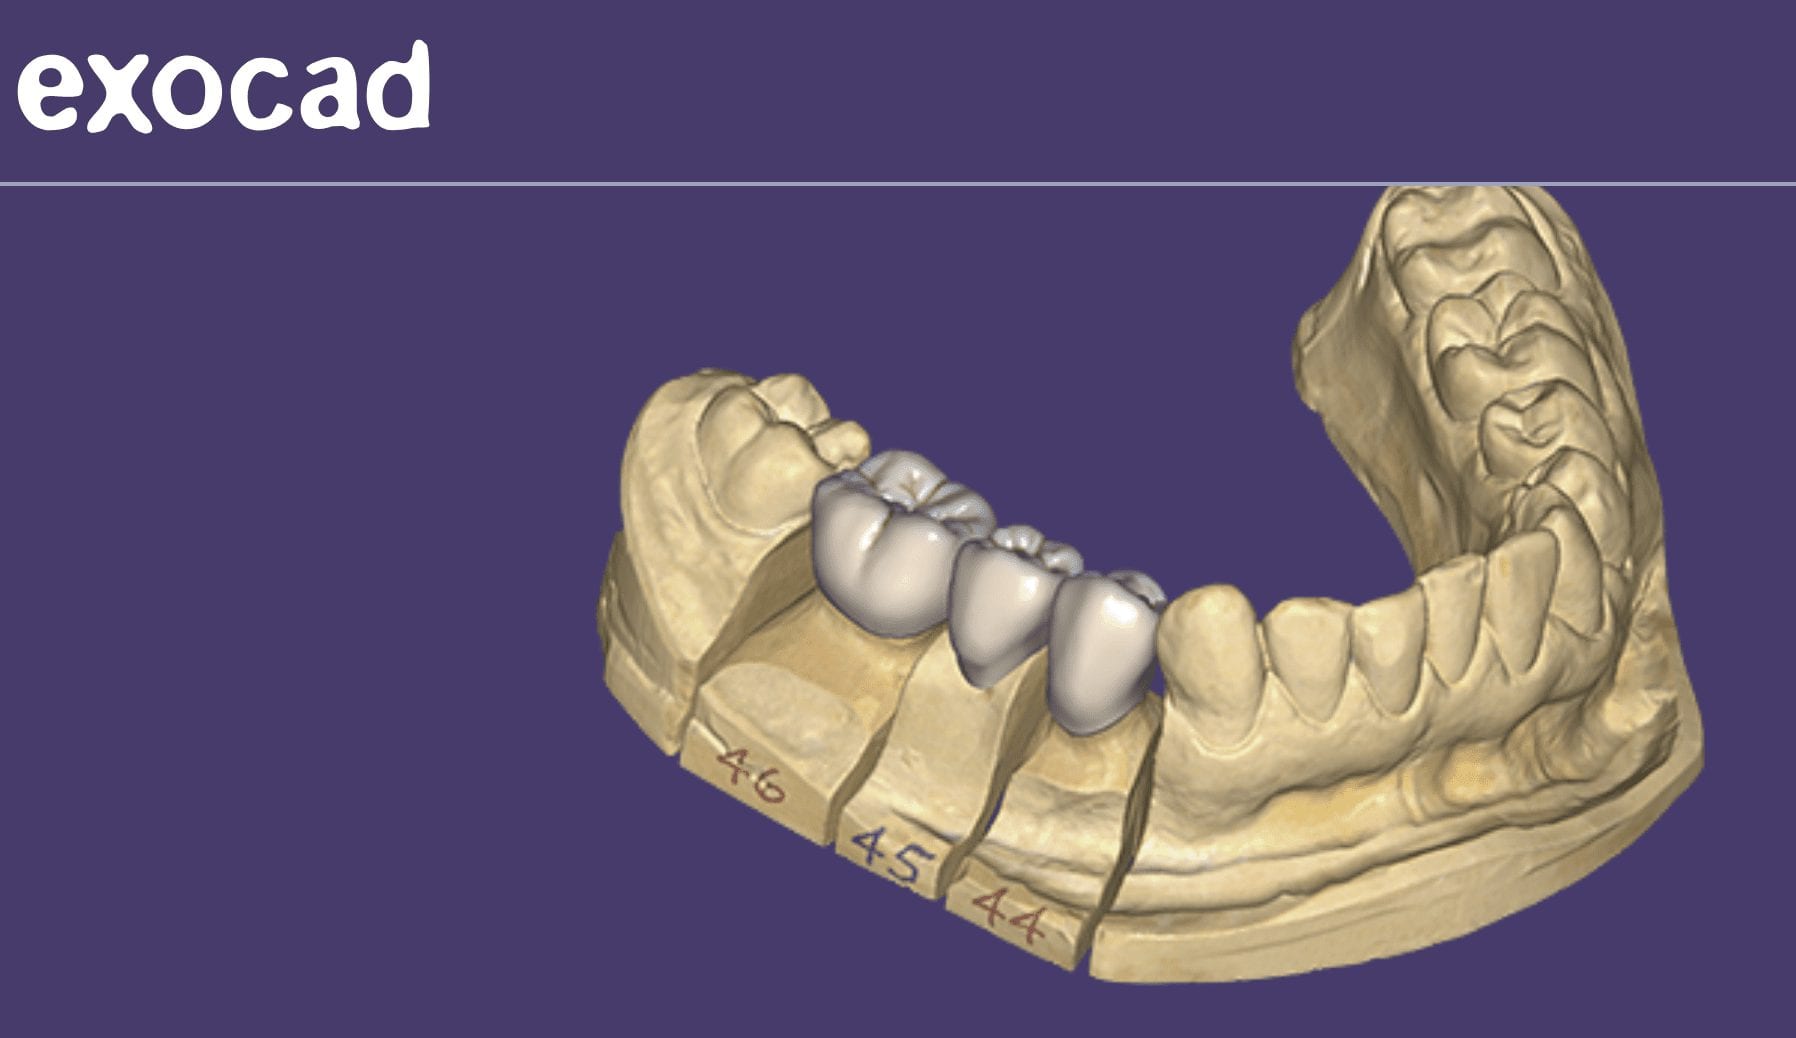

November 15, 2018This is a lesson in chairside efficiency for all CAD/CAM users. Traditionally, you would be forced to prep two teeth and impress them both at same time, but with digital […]

This is a lesson in chairside efficiency for all CAD/CAM users. Traditionally, you would be forced to prep two teeth and impress them both at same time, but with digital […]